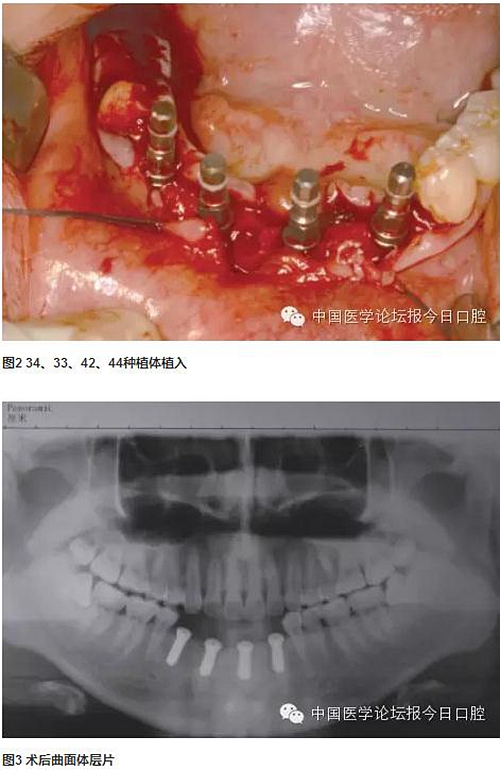

分別于下頜左側(cè)尖牙、下頜左側(cè)中切牙、下頜右側(cè)側(cè)切牙、下頜右側(cè)第一前磨牙位點(diǎn)植入4顆長(zhǎng)度為10mm的常規(guī)頸種植體,3個(gè)月后取模制作研究蠟型,可見(jiàn)種植體開(kāi)口方向均在舌側(cè),較適合制作螺絲固位修復(fù)體。兩次法取模,已釋放材料收縮應(yīng)力對(duì)取模的準(zhǔn)確性產(chǎn)生的影響,確保石膏模型上種植體位置準(zhǔn)確。

技工室制作純鈦支架,聚合瓷修復(fù)牙齒和牙齦形態(tài),患者口內(nèi)試戴,只將一個(gè)種植體的固定螺絲加力,拍片可見(jiàn)其余3顆種植體均實(shí)現(xiàn)被動(dòng)就位,然后將4顆種植體固定螺絲加力,封口(圖2~圖10)。